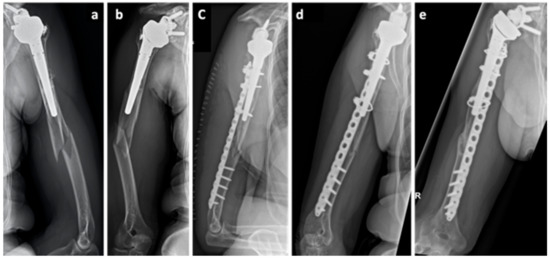

A 51-year-old female Asian patient (body mass 47.7 kg; height: 150 cm; body mass index (BMI): 20.9 kg/m2) was treated with bisphosphonates for osteoporosis for the last 14 years. She presented with acute pain at the right thigh without previous trauma. The radiological examinations included x-rays as well as MRI, both initially evaluated as normal. The following day, the patient presented with an atypical femoral fracture (AFF) (Figure 1d). In retrospect, there was a bone stress reaction as a prodromal sign of an AFF (AFF, Figure 1a–c). Closed reduction and osteosynthesis of the proximal femur was performed (Gamma3 Trochanteric Nail, Stryker, MI, USA). Initially, the treatment with bisphosphonates was continued. In hindsight, this could have prevented the fracture union, however the Task Force of the American Society for Bone and Mineral Research Guidelines [13] were not yet published at that time and, therefore, there was no clear indication for discontinuing the bisphosphonate therapy. Seven months later, the patient presented with a delayed union with persistent pain and lack of radiologic signs of union; she was referred for further osteological treatment with the diagnosis of an atrophic delayed union (Figure 1e). The biomechanical evaluation showed a varus malalignment. The decision was made to furthermore delay revision surgery with fracture reduction, and instead remove the distal screw to allow dynamization of the nail. The antiresorptive therapy was stopped, a vitamin D insufficiency supplemented and the treatment with teriparatide initiated (Figure 1f). The total duration of teriparatide therapy was 24 months. Gradual callus build-up as well as pain reduction was noted in further follow-ups. After completion of the therapy, the patient was pain-free and radiological signs of bony union were present (Figure 1g).

Figure 1. Case 1, X-Rays and MRI of the femur on the day of initial presentation (ac) and one day later (d), showing the diagnosis of an atypical femoral fracture (AFF) under bisphosphonate therapy. X-ray of the hip, 7 months after trauma in the presence of a delayed union (e), after nail dynamization (f), and at the end of the teriparatide therapy (g), 31 months after trauma.